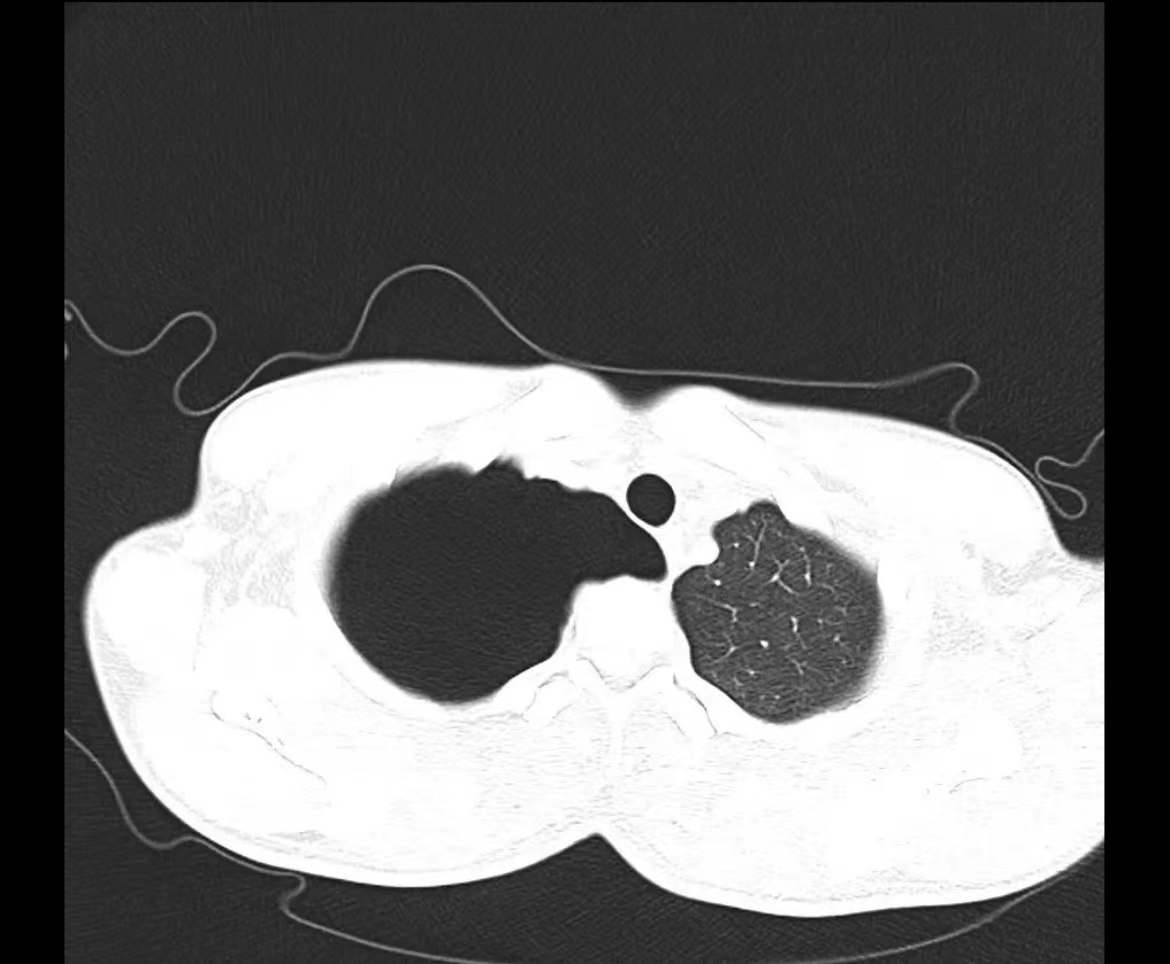

夜班急诊来了一位老大娘,捂着胸口来到CT室说:“医生,快帮我检查一下吧,看我出了什么毛病,胸口痛得厉害,出气都可疼,还闷得慌!”。于是立马登记完检查信息、赶紧给她进行CT扫描,结果一看是气胸,图像如下:

老大娘下了扫描床便说:“都怪我家那儿子,30好几了还不结婚,还没说他两句还给我顶嘴,给我气得直哆嗦,然后我就开始这样了”。看来肺还真能被“气炸”了啊!